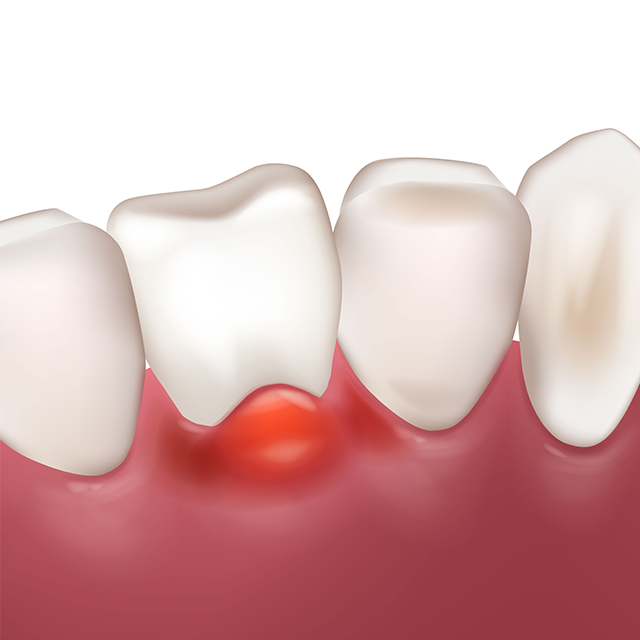

An apicoectomy is a procedure performed when inflammation persists after a root canal treatment.

It involves precisely removing the tip of the tooth root and thoroughly disinfecting the area to preserve the natural tooth.

If Swelling and Pain Persist After Root Canal or Revision Treatment,

the Source of Infection Is Removed.

An apicoectomy, also known as surgical root canal treatment, is a specialized procedure performed when revision root canal therapy is not possible.

During the procedure, the gum is opened, and approximately 3 mm of the tooth root causing the inflammation is carefully removed.

The tip of the root is then filled with a specialized material called MTA.